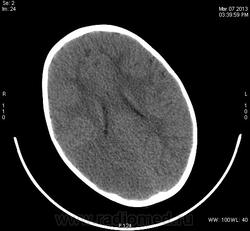

Предположу снижение плотности в правой лобно-теменно-височной области - инсульт в бассейне правой СМА?

Теменная, затылочная справа, ишемический инсульт. С бассейна СМА, как мне видится, "залезает" на бассейн ЗМА, - возможно, вариант развития виллизиева круга.